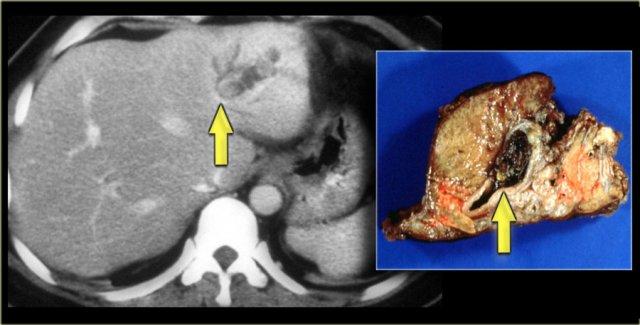

Khối ở thùy gan phải được xác định là áp xe.

Cần lưu ý rằng áp xe gan trong giai đoạn sớm có thể có hình ảnh khá đặc.

Trong chẩn đoán phân biệt, chúng ta cũng cần xem xét khả năng u tân sinh, vì bệnh nhân mắc bệnh Caroli có nguy cơ tăng cao phát triển ung thư biểu mô đường mật.

Cuối cùng, nếu có xơ hóa đáng kể và toàn bộ gan bị ảnh hưởng, những bệnh nhân này sẽ tiến triển thành xơ gan.

Bệnh nhân bên trái đã tiến triển suy gan nặng và được phẫu thuật cắt gan.

Lưu ý tình trạng giãn ống mật trong gan, lách to và giãn các tĩnh mạch bàng hệ.

Trên bệnh phẩm cắt bỏ có dấu hiệu chấm trung tâm (mũi tên xanh dương) và một ổ mủ nhỏ (mũi tên vàng).